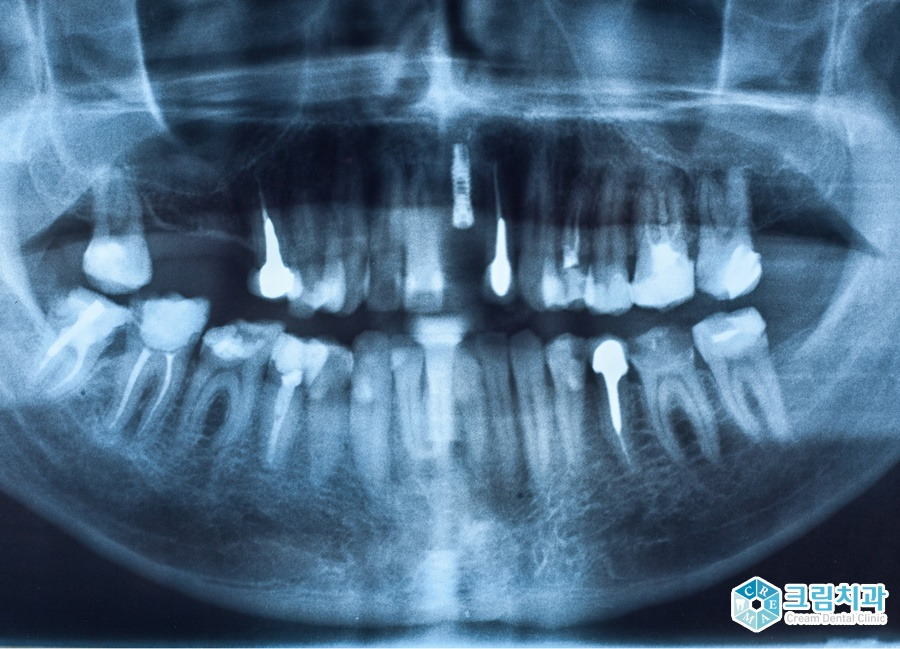

송곳니 임플란트가 어려운 이유는?

상실된 송곳니를 메워줄 가장 좋은 치료법은 바로 임플란트인데요. 송곳니 임플란트는 위치를 비롯한 여러 측면에서 어려운 임플란트에 속합니다. 그 이유는 무엇일까요?

먼저 송곳니 부위는 어금니에 비해 잇몸 뼈가 얇아 인공치근(픽스처)을 단단히 식립하기가 어려운 위치입니다.

또, 기둥 역할로서 저작력 회복 및 인접 치아를 지지해주는 ‘기능적’ 측면과 최적의 위치를 선정해야 하는 ‘심미적’ 측면 모두를 만족해야 하기 때문에 임플란트 중에서도 난도 높은 시술에 속합니다.

잇몸 뼈가 많이 부족할 경우 잇몸 뼈 이식을 진행하는 경우도 있습니다.

특히 위턱의 경우 아래턱에 비해 공간이 부족해 상악동 점막을 들어 올려 뼈 이식 공간을 만들어주는 상악동 거상 임플란트를 진행해야 하는데 이 뼈 이식 또한 의료진의 많은 경험과 노하우, 그리고 실력을 요구하는 시술입니다.